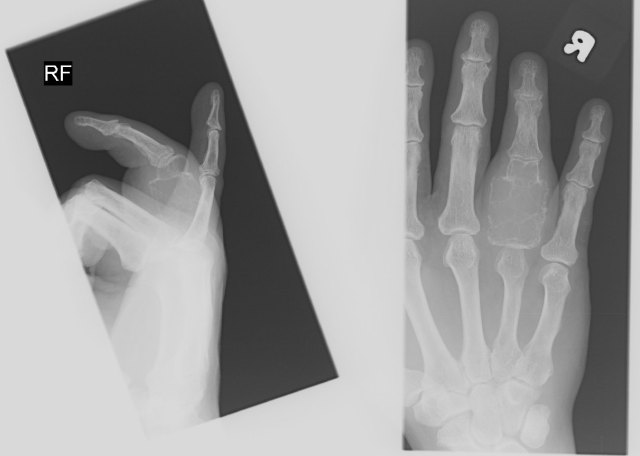

X-rays showed an expansile bony tumour of the proximal phalanx of the right ring finger.

It typically has a “soap-bubble” appearance on x-rays.